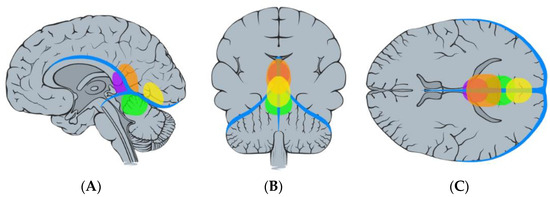

2.2. Volumetric Analysis, Vascular Features, and Tentorial Angle

| Surgical data | Occipital interhemispheric approach | 9 |

| Supracerebellar infratentorial approach | 4 | |

| Retrosigmoid approach | 1 | |

| Type I | Type II | Type III | Type IV | Anterior | Inferior | Posterior | |

| Occipital interhemispheric | 6 | 0 | 1 | 2 | 6 | 0 | 3 |

| Supracerebellar infratentorial | 1 | 4 | 0 | 0 | 1 | 4 | 0 |

| Retrosigmoid | 0 | 1 | 0 | 0 | 0 | 1 | 0 |